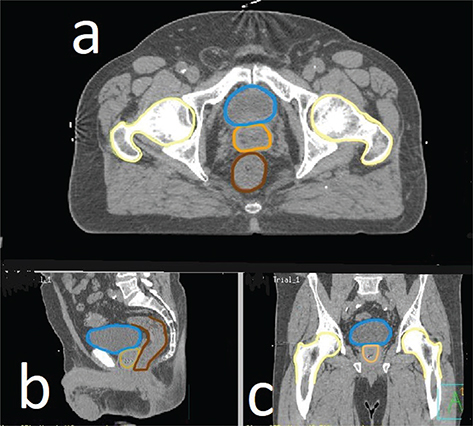

Fig 2

Figure 2. Computerised tomography scans of a male pelvis showed structures that have been converted into a moveable video that appears three-dimensional, through transparent skin. Blue = bladder, beige = prostate, brown = bowel.

De-indentified CT data of a healthy patient, free of disease, were acquired ethically for teaching purposes from a local tertiary hospital. The data were imported into a software called Pinnacle (Phillips et al., 2008) which allows structures to be digitally outlined on a CT image, and then multiple consecutive CT slices are used to create structures with a three-dimensional appearance. The anatomy team identified and traced an outline around individual anatomical structures on dozens of consecutive CT slices in Pinnacle before transferring to VERT. Figure 1a is an example of one CT slice where structures such as the rectum (brown) and hip bones (yellow) have been outlined.